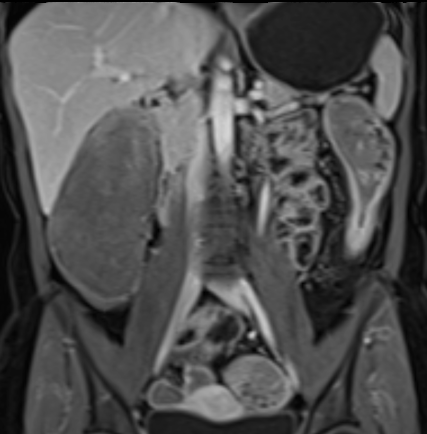

Bệnh nhân nữ 48 tuổi, đang điều trị bằng thuốc kháng TNF, được chỉ định nội soi đại tràng.

Phát hiện hẹp lòng ruột ở đại tràng sigma, không thể vượt qua được khi nội soi.

MR-enterography được thực hiện để đánh giá mức độ lan rộng của chỗ hẹp.

Cuộn qua các hình ảnh.

Ruột non bình thường, nhưng ghi nhận các đoạn hẹp ở đại tràng xuống và đại tràng ngang.

Cả hai đoạn hẹp đều có thành ruột dày đến 8 mm và ngấm thuốc rõ rệt theo kiểu niêm mạc ở đại tràng xuống và kiểu phân lớp ở đại tràng ngang.

Giãn ruột trước chỗ hẹp được ghi nhận ở cả hai đoạn.

Do các chỗ hẹp này không hiện diện khi nội soi đại tràng trước khi điều trị kháng TNF, nhiều khả năng chúng đã hình thành trong quá trình điều trị.

Do đó, quyết định phẫu thuật cắt đại tràng gần toàn bộ với miệng nối hồi-sigma đã được đưa ra.